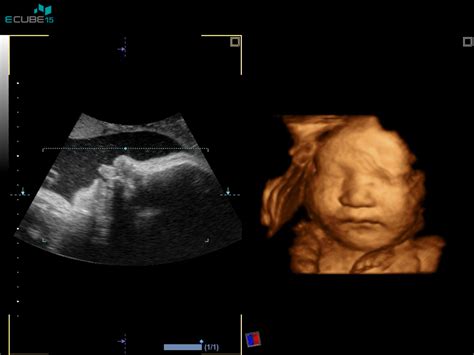

Predležeča posteljica se večinoma diagnosticira v drugi polovici nosečnosti. Večinoma se diagnosticira med ultrazvokom na enem od rutinskih predporodnih obiskov. Test uporablja zvočne valove, da pokaže, ali posteljica prekriva odprtino od maternice do materničnega vratu. Zahvaljujoč rednim ultrazvočnim pregledom jo odkrijejo še pravi čas in jo spremljajo.